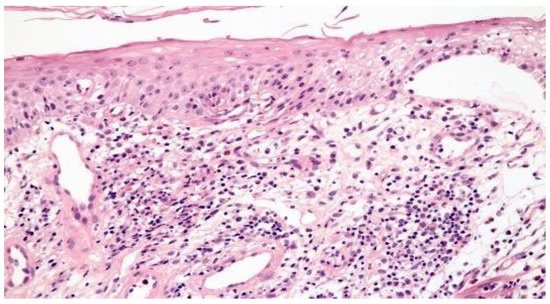

Chronic gastritis was identified in the body in 52 patients (89.7%) and in the antrum in 51 patients (87.9%), with a predominance of mononuclear cells in 37 patients (63.8%) and discrete infiltrate of the lamina propria in 35 patients (60.3%). Histopathological alterations were present in 18 of 19 patients (94.7%) of the patients with erosive gastritis, and in 13 of 13 patients (100%) with erythematous gastritis. Focally enhanced gastritis (FEG) was identified in four patients (6.9%), all of whom were H. pylori-negative (Figure 2), two with erythematous gastritis and two with erosive gastritis. Epithelioid granuloma was not found.

Figure 2.

Focal enhanced gastritis: mononuclear inflammatory infiltrate associated with focal destruction of glands. Lesion intensity contrasts with slight inflammatory infiltrate in the remaining lamina propria. (a) H&E × 40; and (b) H&E × 100.